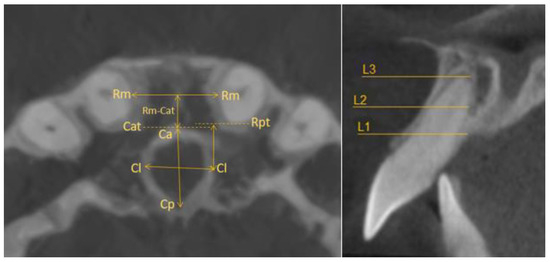

- Horizontal plane separately for each level—L1, L2, and L3:

- Incisive canal width—|Cl-Cl|.

- Antero-posterior IC—|Ca-Cp|.

- Distance between the most mesial point of the root and the tangent passing through the most anterior point of the incisive canal—|Rm-Cat|.

- Distance from Cl to the posterior edge of the incisor root—|Cl-Rpt|.

- Distance between roots |Rm-Rm|.

- Sagittal plane:

- Angle formed by the long axis of the incisor and the palatine plane—CP angle.

- Angle formed by the long axis of the incisive canal and the palatine plane—IP angle.

- Coronal plane:

- Angle formed by the long axes of the central incisors (values above zero for convergent roots, negative values for divergent roots).